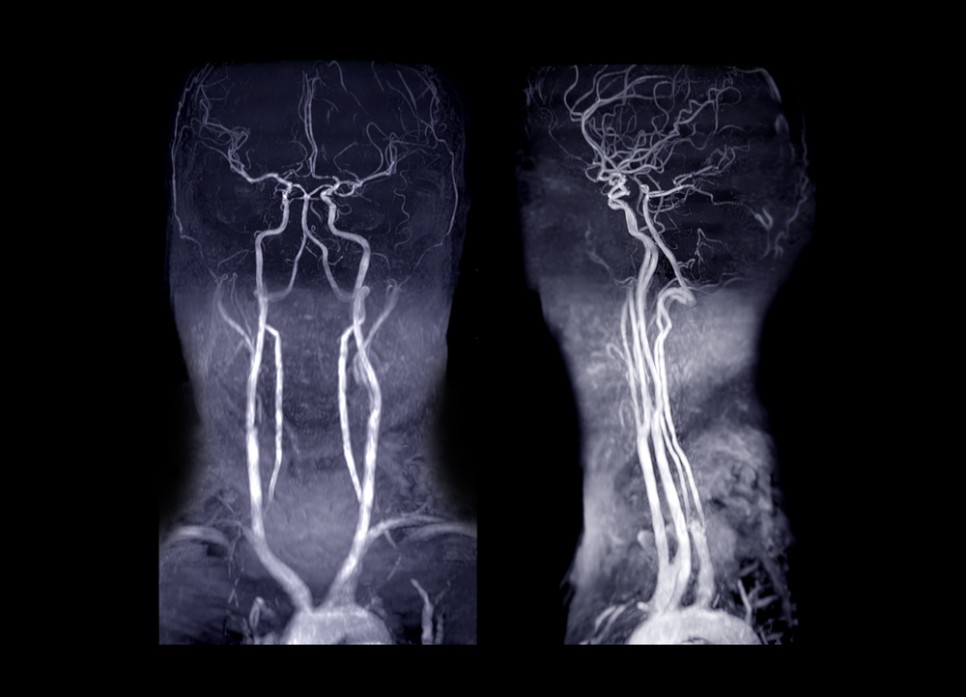

경동맥 협착증은 여러 진단 검사를 실시하고 심하지 않은 경우 약물 치료를 합니다. 경동맥협착증의 진단검사는 경동맥초음파검사, 컴퓨터단층촬영(CT), 자기공명영상(MRI), 경동맥혈관조영술 등을 시행합니다. 혈관조영술은 요즘에는 잘 쓰이지 않아요.

경동맥 초음파 검사(동맥 초음파 검사)는 목에 있는 동맥을 초음파로 조사하는 검사입니다. 이 경동맥 초음파 검사를 통해 경동맥의 동맥 경화 검사나 편두통의 원인 확인, 뇌 혈액의 순환 상태를 확인할 수 있습니다.